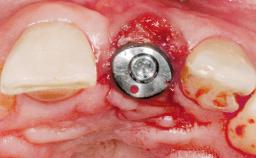

Immediate Flapless Placement of an Implant in a Maxillary Left Central Incisor Site

A 42-year-old female patient was referred to our clinic at the School of Dentistry of the University of São Paulo in November 2004, presenting a deficient restoration in the upper left central incisor. The clinical examination revealed no gingival retraction or any signs of gingival inflammation and, therefore, previous periodontal treatment was not considered. The patient presented a high lip line at full smile and a thin tissue biotype. This combination characterized a high-risk situation from an anatomic point of view, which required careful preoperative planning and cautious surgical execution.

Placement Protocol Immediate implant placement

Socket Morphology Single-root socket

Socket Integrity Sufficient, with intact bone walls

Bone Volume Sufficient, with intact walls